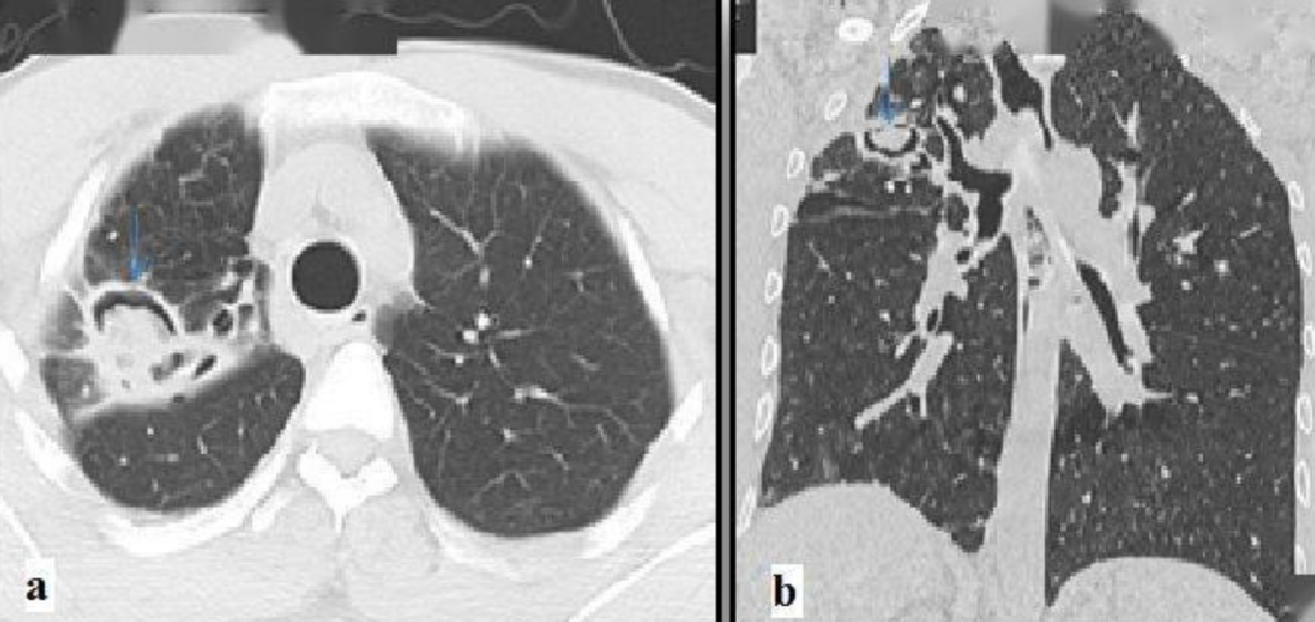

主要表现:最常见、最典型症状就是反复咯血,从痰中带血到大量咯血都有可能,这是因为真菌球摩擦空洞壁的血管所致。此外,还有慢性咳嗽、咳痰、盗汗、体重减轻、乏力等慢性消耗症状。胸部CT上常能看到一个典型的“新月征”空洞,里面有一个可移动的团块影。

影像学:胸部高分辨率CT是重中之重。它能清晰显示真菌球、空洞、“晕轮征”(侵袭性感染早期典型表现)等关键证据。